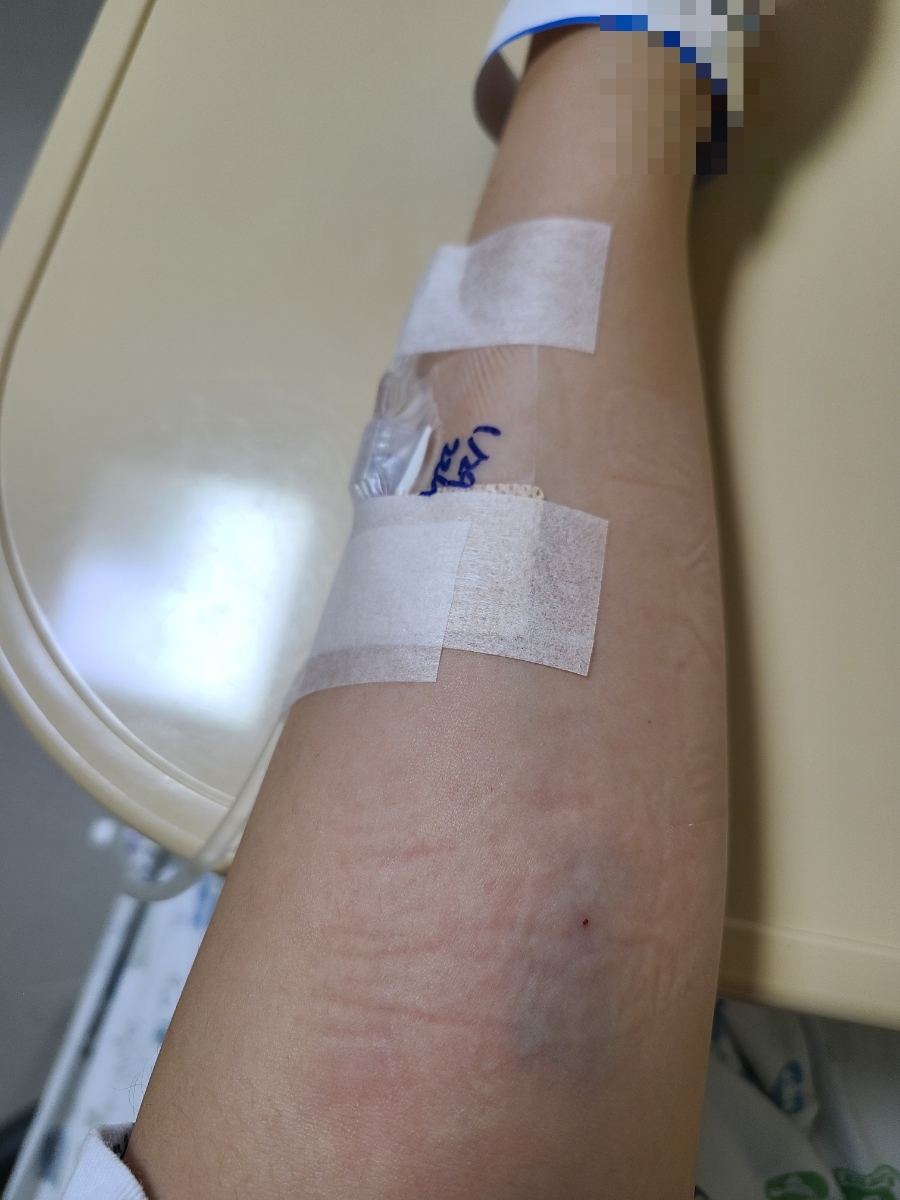

가습기를 틀고 잤는데 일어났더니 목이 건조해.’내일 아침은 실패했구나’라는 생각이 들었다.당연히 병원 내에서 숙면을 취하는 것은 불가능하지만(시간에 맞춰 혈압과 체온 등을 측정하기 때문에) 나름대로 나쁘지 않았다. 1인실 만세!! 어제 움직일 때마다 조금 아팠던 링거의 위치를 변경했다.

바꾸길 잘했다 바꿔서 그들은 어떻게 움직여도 하나도 아프지 않아!! 멍을 들었다. 나의 수술 예정 시간은 오전 9시.8시 30분까지 학부모 한 명이 상주해야 해서 어제 생일의 주인공인 엄마를 불렀다.8시 50분쯤 간호사가 5층 수술실로 가자고 했다. 걸어서 엘베타고행 회복실 앞에서 기관지를 확장시키는 흡입기 같은 것을 1분 동안 하라고 해서 했다.다 하고 5분정도 기다리면 수술실에서 저를 부르셔서 어머니와 헤어져 그대로 입실.수술실은 생각보다 작았다.수술상도 다 차려져 있더라.누워서 준비하고 있으면 마취과 원장이 와서 졸릴 것 같아요~라며 마취가스를 뿌렸지만 두 번 정도 마시고 나서 정신을 차려보니 회복실이었다.옆에 어머니가 앉아 있었다.조금 몽롱했지만 어머니에게 했던 이야기가 모두 생각난다. 와, 바로 기절했어 수술실이 생각보다 작다… 이런 얘기. 걸을 수 있을 것 같아서 일어났는데 제지 당해서 침대째 병실로 왔다.병실에 온 시간은 9시 40분?50분 정도였다.1시간도 안 걸렸네.병실에 오자마자 간호사 선생님이 혈압, 체온 등을 재서 거울에 편도선이 사라진 것을 확인하고 엄마가 입속 사진을 찍어달라고 했어ㅋㅋㅋㅋㅋㅋㅋㅋ